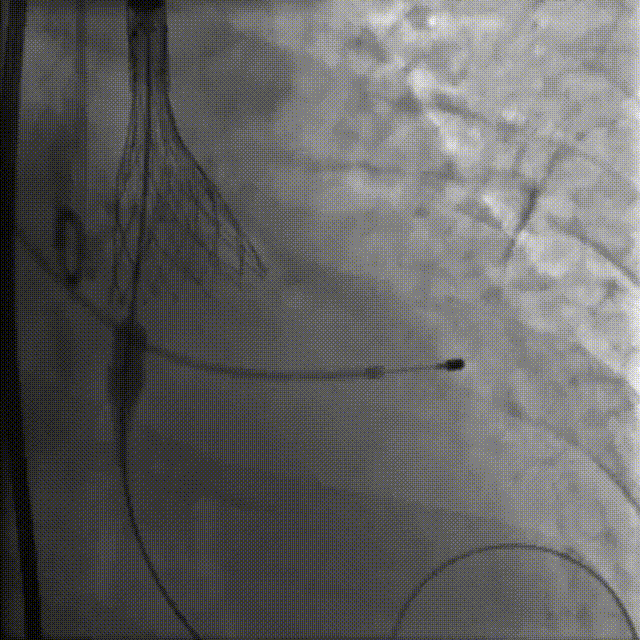

手术影像

主动脉根部造影

20mm球囊预扩后瓣膜开始定位

工作位造影:左右窦侧瓣架偏深

回收后重新调整释放

工作位造影:位置理想

瓣膜逐个缓慢脱钩

23mm球囊后扩改善形态

最终造影:位置理想,形态良好,无漏